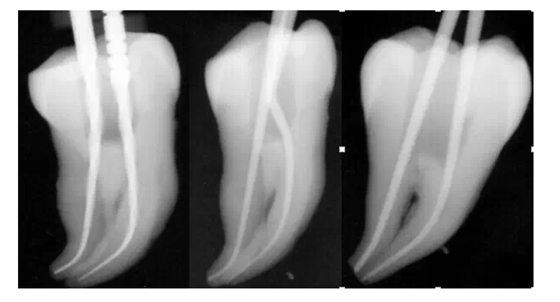

很意外吧,其實就是這么簡單,第二步,一支鎳鈦銼,全程制備。以下是筆者用一支鎳鈦銼制備離體牙后試主尖的X-ray影像。

彎曲根管制備——ONE FILE FLEX共兩步,同樣是這么簡單。ONE FILE FLEX X-ray片實拍得悅 ONE FILE FLEX的使用參數(shù):轉(zhuǎn)速:450轉(zhuǎn)/分 扭矩:1.0-2.0